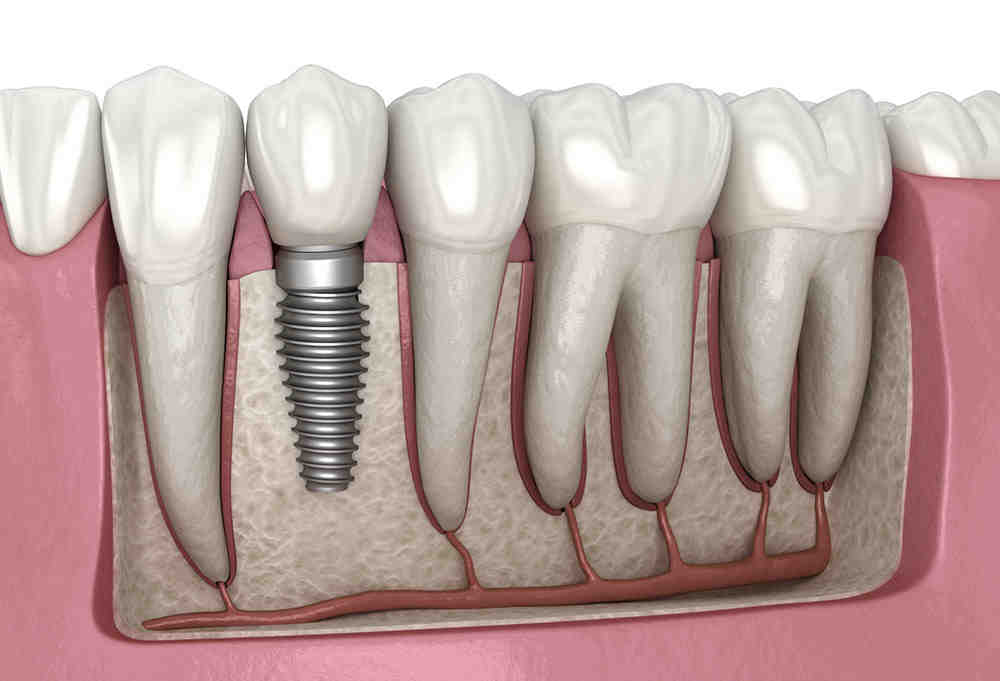

With careful positioning, an implant can be used to support one or more crowns. Some techniques use only a few implants to support a full tooth arch. As you make your decision to have dental implants, be sure to discuss these options with your implant dentist in detail.

Your dentist can place an implant at each end of the space. The implants will hold the crowns and the crowns will hold 1 to 3 pontics between them. See the article : Dental Implnat. Thus, in total, two dental implants can replace up to five teeth.

Replacement of four or more teeth If you are missing four consecutive teeth, we only need to place two implants which can then suspend two false bridge teeth between them. This may interest you : Do dental implants come out.